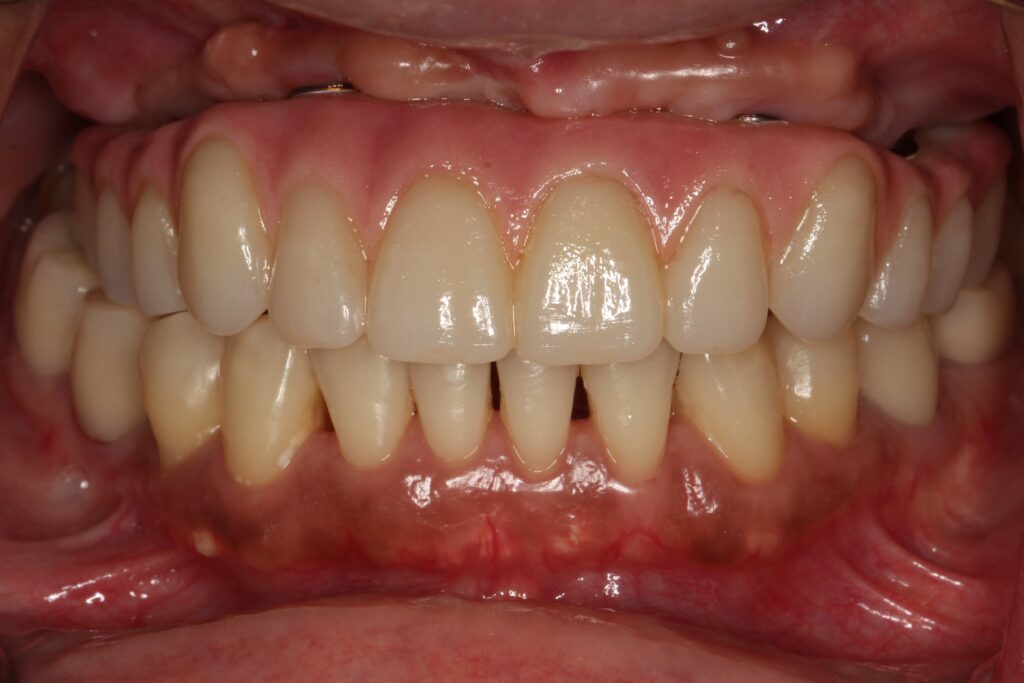

A selection of full arch fixed implant bridge patients after 5 years of wear

Oral Surgeons – Dr Han Choi, Dr Sam Goldsmith, Dr Rajiv Rajpal NSOMS

Prosthodontist – Dr Alan Payne NSOMS/Northland Prosthodontics

Dental technicians – Hosaka Takashi, DT Denture Design, Auckland, CJ Park, Project Dentistry, Auckland and Osteon Medical, Melbourne, Australia.